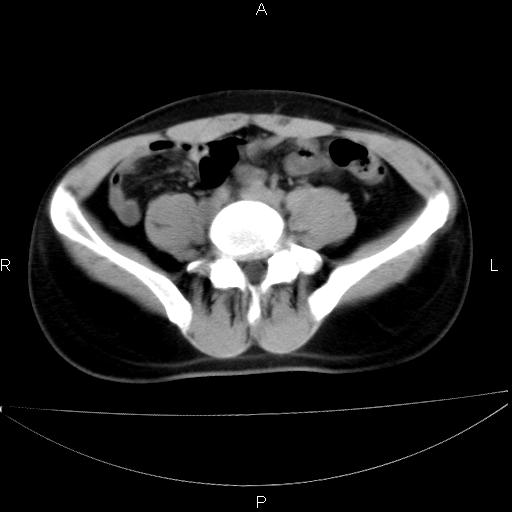

男 25岁 自述 尿频尿急,排尿困难20多天.无腰痛, b超说左肾盂轻度积水,左输尿管上端扩张.未见结石影. ct我看双侧肾盂轻度积水,双输尿管上端都扩张,大家看看能看见结石吗?

双肾轻度积水,双侧输尿管上段扩张(原因待查)。

双输尿管扩张下端未见高密度结石和输尿管晕轮征,不好说是结石.增强后如何?

双侧输尿管上端扩张,未见明确结石,可进一步ivp检查。

双肾盂及双输尿上段轻度积水,双输尿管未见明显结石影。